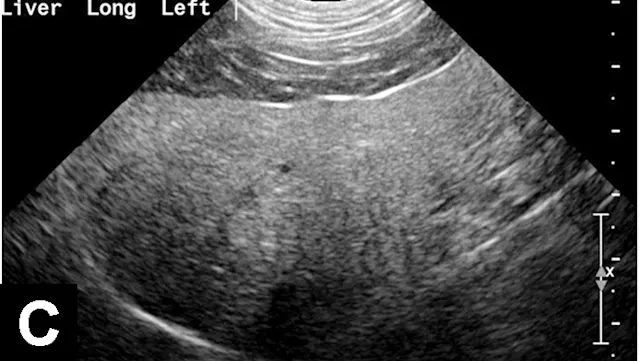

Figure 2A

Liver with normal parenchymal echogenicity in a dog (A); however, cytologic examination via fine-needle aspirate showed diffuse infiltration of malignant mast cells. Liver with normal ultrasonographic appearance in a cat (B); however, cytologic examination via fine-needle aspirate showed diffuse infiltration with lymphoblasts indicative of lymphoma.